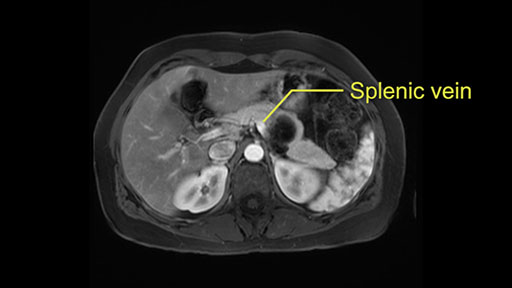

Other slowing down moments with this procedure include dissection of the splenic vein and splenic artery. These are technically challenging moments and important moments where care needs to be taken. Not only to avoid bleeding and injury to the vessels but also to ensure an adequate margin.

The second slowing down moment or consideration I give to a distal pancreatectomy is the anatomy of the portal vein and the splenic artery. And so I look here and the anatomy is pretty straightforward. The splenic vein comes off normally and runs behind the pancreas and I can see the artery superior to that, again coming off in a normal manner from the celiac axis. So those two things, the portal vein and the splenic artery will be taken normally in this procedure.

I think the splenic vein, once I have slowly teased it off from the cyst and from the retropancreatic parenchyma, I would put a vessel loop around it to serve as a traction. So once you have the vessel loop or probably umbilical tape, to retract or pull the pancreatic parenchyma while we slowly tease it off and try to move superiorly to be able to expose the splenic artery. That is again another slow-down moment because sometimes we think that it is the splenic artery at the superior edge of the pancreas, but it could also be the hepatic artery as it branches from the celiac artery.

So what I would normally do in these patients, I would look at the abutment of any other organs, one, which is here, potentially the adrenal gland and two the small bowel. And two, look at the distance from the vessels which I would normally do in a coronal view. So you can easily measure the distance and third I look at the insertion of the inferior mesenteric vein. Now we can probably also see that on here. Although it's better on a CT scan and it's better on a coronal view, you want to know where the inferior mesenteric vein comes into either the splenic or the SMV, because that is typically a very important slow down moment when you mobilize the lower portion of the pancreas knowing where the inferior mesenteric vein comes in either the splenic vein or the SMV. So those are I think the three most important points for the CT scan.

If you hang the pancreas then you move down towards the right side of the patient. You know your first slowing down moment is where the inferior mesenteric vein comes in the splenic vein or into the superior mesenteric vein, you have looked at that at the scan, so you know where to expect it. You can do two things in a procedure where you can preserve the splenic vein, you can preserve the IMV as well. But in this case where you want to do an oncologic resection with splenectomy, you will transect the inferior mesenteric vein.